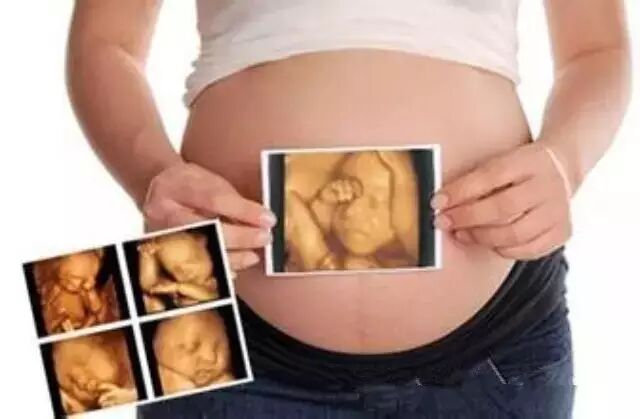

号外号外,4D大片震撼来袭—德保最新推出宝宝4D大片,这等好事,妈妈们怎么不去体验

记得在谈恋爱的时候,小情侣都会手拉手,去电影院买上一盒爆米花,看场哭的稀里哗啦的爱情电影。现成了夫妻,看电影的时间也少了,不过机会来了,孕妈咪可以带着准爸爸一起来看胎宝宝的4D影像,共同见证胎宝贝的成长瞬间。

每个准妈妈都是兴奋和激动的,我家宝宝长什么样呢?是像他爸爸,还是像我呢?宝宝又动了,他在干什么呢?是自己玩呢,还是睡觉呢?是皱眉呢,还是笑呢?现在,四维彩超就可以给你一个准确的答案!这就是四维彩超带来的魅力,它能更清晰、更立体地把宝宝的一言一行,一举一动,生动地传达给孕妈妈,让孕妈妈和宝宝穿越时空提前相见